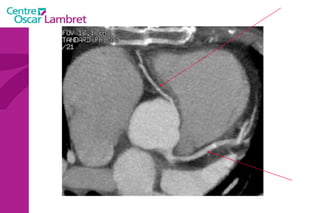

Le cœur  se situe au milieu du thorax, sur le diaphragme, la pointe tournée vers la gauche. L’appareil circulatoire

L’appareil circulatoire Le coeur  est un organe formé essentiellement d'un muscle, le myocarde, lequel est entouré d'un "sac" séreux, le péricarde et tapissé à l’intérieur par une fine membrane, l'endocarde.

Le coeur  comprend quatre cavités :  deux cavités droites, formées par l’oreillette (ou atrium) et le ventricule droit.  deux cavités gauches, formées par l’oreillette (ou atrium) et le ventricule gauche.  Les cavités droite et gauche sont totalement séparées par une cloison (septum).  Ces cavités sont connectées à des veines et des artères qui conduisent le sang venant ou partant du coeur.  L’appareil circulatoire

Les 2  atriums  ont un petit diverticule : les auricules Le cœur repose sur le diaphragme et est situé au niveau de la partie antérieure et inférieure du médiastin. Le coeur est bordé latéralement par les poumons qui le recouvre partiellement. Les 4 cavités du coeur sont limitées par des sillons. Le  sillon coronaire le sillon inter atrial  Le sillon inter ventriculaire ou septum L’appareil circulatoire